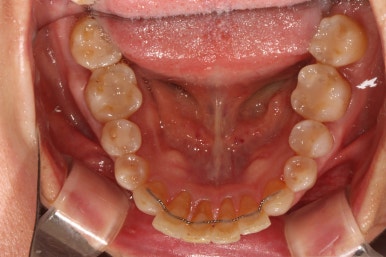

아래 앞니만 조금 더 가지런해지면... 될 것 같은 느낌이네요.

그리고 교합면 사진을 통해 전체적인 진행 상태도 파악할 수 있죠.

이제 정말 많이 배열이 완성되었습니다. 아래 앞니를 배열시키느라 시간이 조금 더 걸렸던 것 같아요.

비록 앞니가 깨진 것이 조금 눈에 띄긴 하지만... 환자분은 배열만 해도 매우 만족한다 하셔서 이렇게 치료를 마무리 하였습니다. 끝까지 배열이 어려웠던 아래 앞니의 가지런함이 눈에 띕니다.

씹는면에서 보아도 상당히 가지런히 완성된 것을 보실 수 있습니다.

교정치료가 끝나면 혀쪽에 유지장치를 붙여드리는데요, 치석이 보다 덜 생기도록 하기 위해서 치아 표면 그대로의 모양을 따라가는 와이어를 제작하여 부착해드리고 있습니다.

조금 더 비용을 들이더라도 정성담긴 모양의 유지장치입니다!!

치아 사이 공간까지도 완벽하게 밀착하고 지나가야 좋은 고정식 유지장치입니다. 그래야 치석도 덜 생기고 관리가 편해지시거든요..

교정치료가 끝나고 2년 뒤 내원하셨을 때의 구강내 사진입니다.

스크롤을 위아래로 이동해가며 보시면 아시곘지만, 치열의 변화가 거의 없어요!

교정유지장치 끊어짐 없이 아주 깔끔하게 잘 관리되고 있습니다.

조금 힘드셨겠지만, 철저한 구강위생보조용품 사용으로 더욱 완벽히 관리해주시고 있는 모습입니다.

보통 교정유지장치가 있는 경우 6개월에 한번씩 내원하셔서 스케일링 받으시길 권해드립니다!!